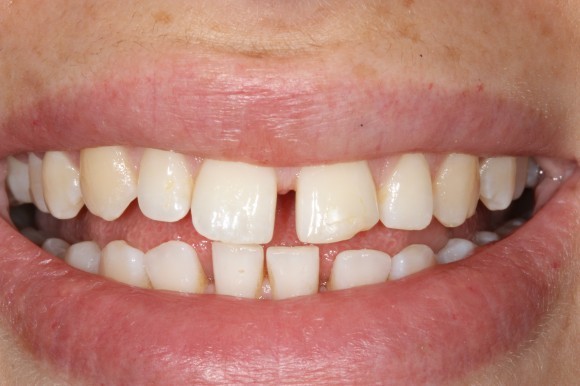

Gapped teeth, which are also called diastema, cause distinct gaps between the teeth. Diastema is a term used most often for the gap between the front two upper teeth, the most common gap in the mouth. 50-60% of children under the age of 5 have this gap, and it will usually close on its own by the age of 8 or 9. If the gap hasn’t closed even after the adult canine and incisor teeth have come in, it may not close on its own at all.

Aside from genetics, there are a few other reasons why gaps in the teeth may develop. For example, if there is a size mismatch between your child’s jaw and teeth size, there may be extra room in the jaw for the teeth to space apart. Additionally, childhood habits like pacifier use or thumb-sucking can also result in gaps between the two front teeth.

Another cause of gaps in the teeth is frenum issues. The maxillary labial frenum is a strip of tissue that connects the underside of the upper lip to the gum tissue between the two front teeth. If this strip of tissue is too thick, it can prevent the two front teeth from closing together.

Gaps in the teeth can be closed in a number of ways. The most common fix for gapped teeth is through the use of orthodontic braces. But other cosmetic procedures can be used to close the gap, including dental veneers, a dental bridge or implant or even partial dentures. The treatment depends on the location of the gap and why it’s occurring.